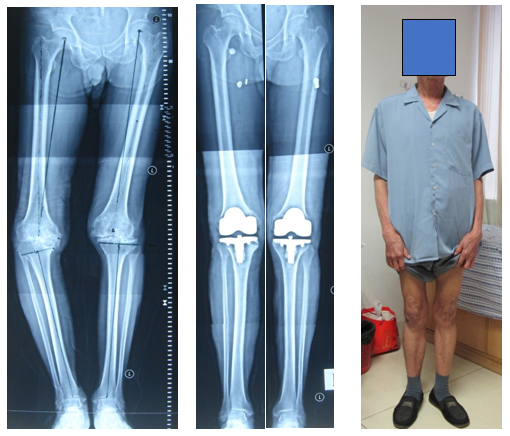

68岁阿叔,左膝关节疼痛2年了,他的要求是希望手术后除了不痛,还要求以后可以踢毽子和游泳,考虑到他膝关节内侧软骨磨损并不是完全磨损,结合他个人的手术期望值,治疗方式为:胫骨高位截骨术,术后第二天就下地行走,术后一个月完全恢复正常,非常满意

如果内侧软骨完全磨损,达到骨磨骨的程度,患者年龄又较大,则可以选择膝关节内侧单髁置换术,出血少,创伤小,恢复快,功能好。

82岁的阿伯,右膝疼痛10年,考虑到他年纪大,膝关节仅仅是内侧软骨磨损,达到骨磨骨的程度,治疗方式为:膝关节内侧单髁置换术,风险小,微创,术后5天顺利康复出院

71岁的陈伯,双膝疼痛10余年。X线片提示双膝是晚期骨关节炎,非常明显的顺风腿。双侧做了人工膝关节表面置换术后,术后第二天就可以下地走路,目前可以正常出行,生活健康